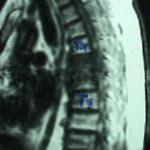

Εικ. 3: Μαγνητική τομογραφία της Θ.Μ.Σ.Σ. οβελιαία τομή, ακολουθία Τ1 & Τ2

Παρατηρούμε την αλλοίωση του σήματος σε όλες τις ακολουθίες, ενδεικτικό της ύπαρξης λοιμώξεως στο μεσοσπονδύλιο δίσκο και εκατέρωθεν αυτού στα σπονδυλικά σώματα. Είναι εμφανής η ύπαρξη επισκληριδίου αποστήματος στο σύστοιχο επίπεδο Θ5-Θ6 (ζ,η)